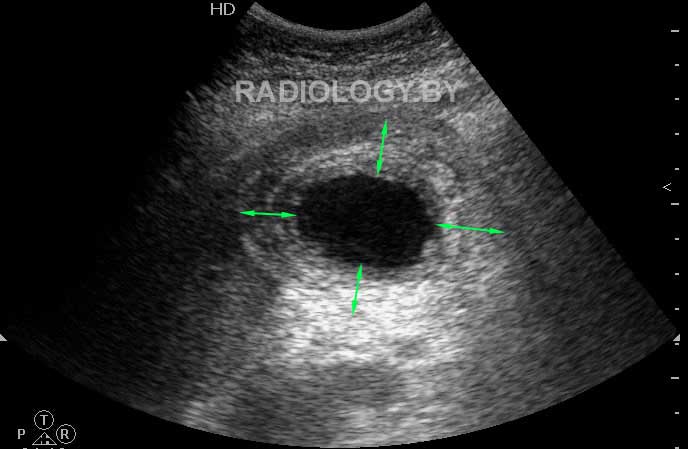

Женщина средних лет с болями в правом подреберье поступила в приемный покой хирургической клиники.

Выявлены следующие изменения желчного пузыря

Ваше заключение? Оцените примерную толщину стенки желчного пузыря.

Acute cholecystitis; sludge, gall stones. Predicted wall thickness about 8-12 mm.

Я бы написал:"УЗ картина хронического калькулезного холецистита в фазе обострения (вероятно, с перипроцессом)".